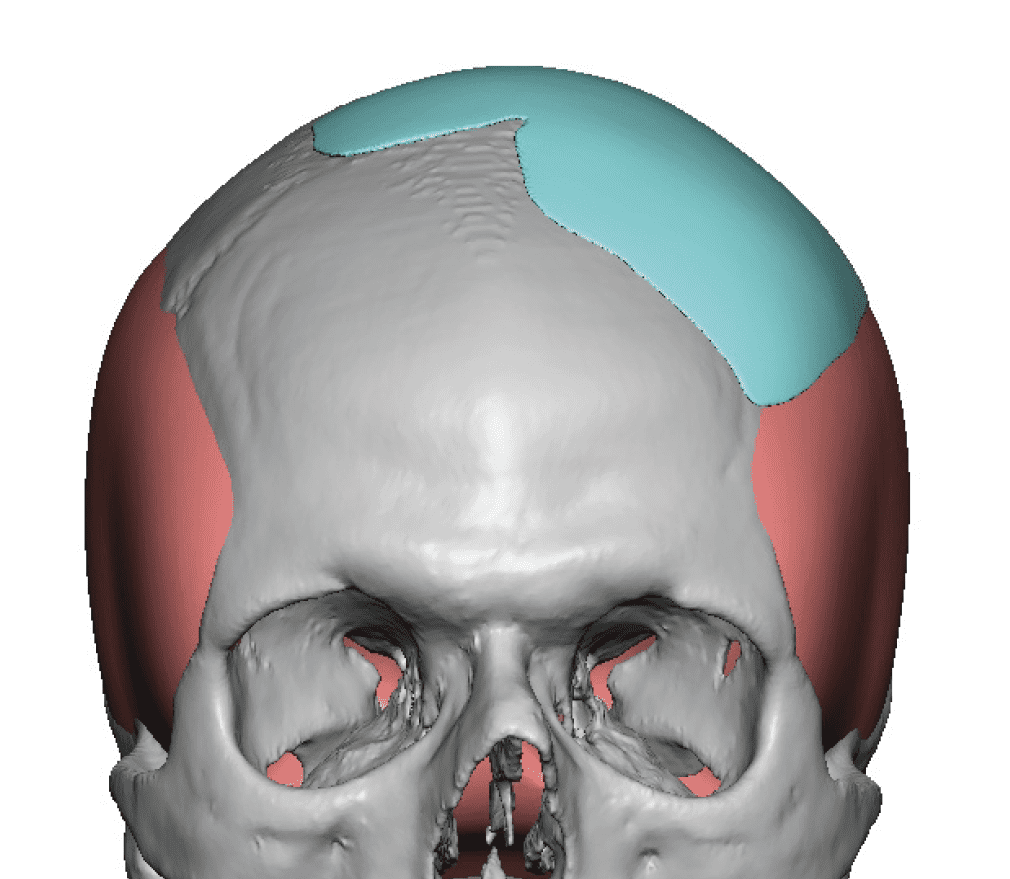

Desire for change of head shape from front view form an inverted V shape to a rounder and wider head shape.

Placement of custom extended forehead-temporal implants through incisions in the crease behind the ear. (he had a prior back of head skull implant which is green in the implant designs and which the head widening implants partially covered it)

Desire for change of head shape from front view form an inverted V shape to a rounder and wider head shape.

Placement of custom extended forehead-temporal implants through incisions in the crease behind the ear. (he had a prior back of head skull implant which is green in the implant designs and which the head widening implants partially covered it)